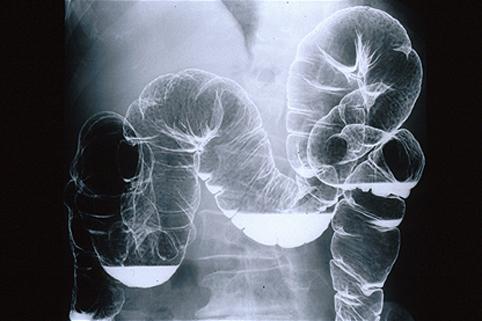

Criteria of Hist.ClassificationMalignant Lymphoma/MLP type

LocationLarge intestine(Colon)/More than one of the above

Technique, MethodX-ray

Size1 - 9

Multiple neoplasm in same organBoth of Syn. and metachronous

Multiple neoplasm in anotherBoth of Syn. and metachronous